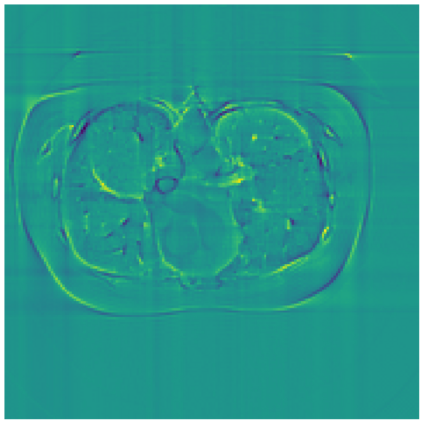

Sparse-view computed tomography (CT) -- using a small number of projections for tomographic reconstruction -- enables much lower radiation dose to patients and accelerated data acquisition. The reconstructed images, however, suffer from strong artifacts, greatly limiting their diagnostic value. Current trends for sparse-view CT turn to the raw data for better information recovery. The resultant dual-domain methods, nonetheless, suffer from secondary artifacts, especially in ultra-sparse view scenarios, and their generalization to other scanners/protocols is greatly limited. A crucial question arises: have the image post-processing methods reached the limit? Our answer is not yet. In this paper, we stick to image post-processing methods due to great flexibility and propose global representation (GloRe) distillation framework for sparse-view CT, termed GloReDi. First, we propose to learn GloRe with Fourier convolution, so each element in GloRe has an image-wide receptive field. Second, unlike methods that only use the full-view images for supervision, we propose to distill GloRe from intermediate-view reconstructed images that are readily available but not explored in previous literature. The success of GloRe distillation is attributed to two key components: representation directional distillation to align the GloRe directions, and band-pass-specific contrastive distillation to gain clinically important details. Extensive experiments demonstrate the superiority of the proposed GloReDi over the state-of-the-art methods, including dual-domain ones. The source code is available at https://github.com/longzilicart/GloReDi.